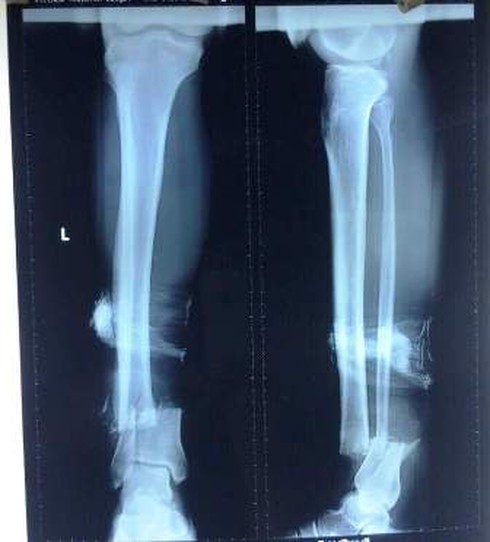

Hình ảnh chụp Xquang cho thấy chân bệnh nhân gần như đứt lìa, chỉ còn dính lại một ít da. |

Tại BV Việt Nam – Thụy Điển Uông Bí, sau khi tiến hành hội chẩn các bác sĩ kết luận ông Kh. bị vết thương đứt gần rời cẳng chân trái, gãy hở 1/3 xương cẳng chân trái, đứt gân cơ và dây thần kinh, mạch máu và được chỉ định phẫu thuật cấp cứu xử trí vết thương.